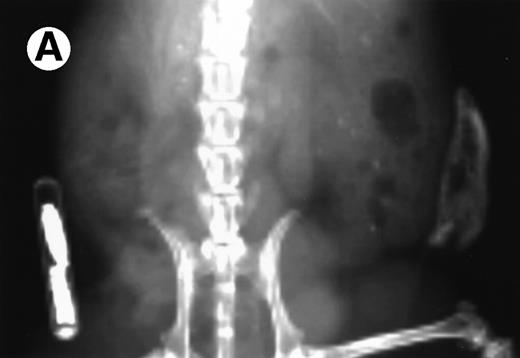

Growth of the myeloma cells was associated with increased blood Ca levels (summarized in Fig 5), suggesting anomalies in bone remodeling. Immunohistochemical examination of the kidneys showed varying amounts of light chain deposits (not shown). Decalcified bone sections stained for TRAP showed markedly increased osteoclast activity (Fig 6). Severe loss in human bone density was readily visible upon x-ray examination in all cases. Although density loss was severe in all mice, the degree of human bone resorption varied. An example depicting a moderate level of density loss is presented in Fig 7.

Loss in density of human bone in myeloma-bearing SCID-hu mouse as seen by x-radiography. Human bones are visible in the right-hand side. The highly contrasted devices visible in the bottom left corner are implant transponders used to identify the mice. (A) Myeloma-bearing mouse (patient no. 6): (B) Age-matched control SCID-hu mouse.